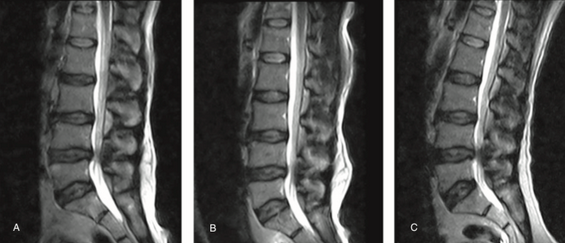

腰椎管狭窄的MRI检查!

腰椎MRI阅片,一定要注意这些细节!